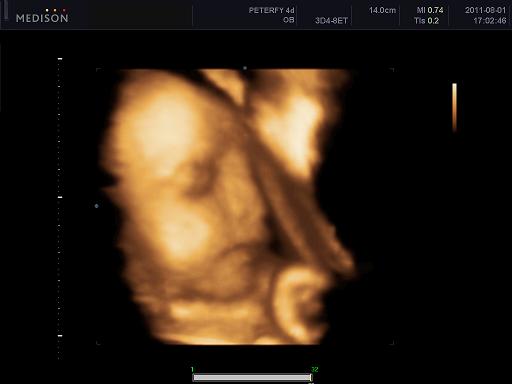

Velünk minden oké szerencsére, dundisodok én is, a baba is tök szuperül van ééééés tegnap voltunk végre 4D-n, annyira nagy élmény volt lányok!!!! Nem is gondoltam h ez ennyire jó dolgo, azzal együtt, hogy Alma nagyon bújócskázott, végig az arcát simizte meg takargatta, csak néha kaptunk egy kis mosolyt de imádom, végtelenül nagy boldogság ez a kis csöppség!!!!! :)

1250 grammos és kis ficánka, meg a szonográfus csaj is mondta hogy mennyire kis cserfes már most! :D

Kép